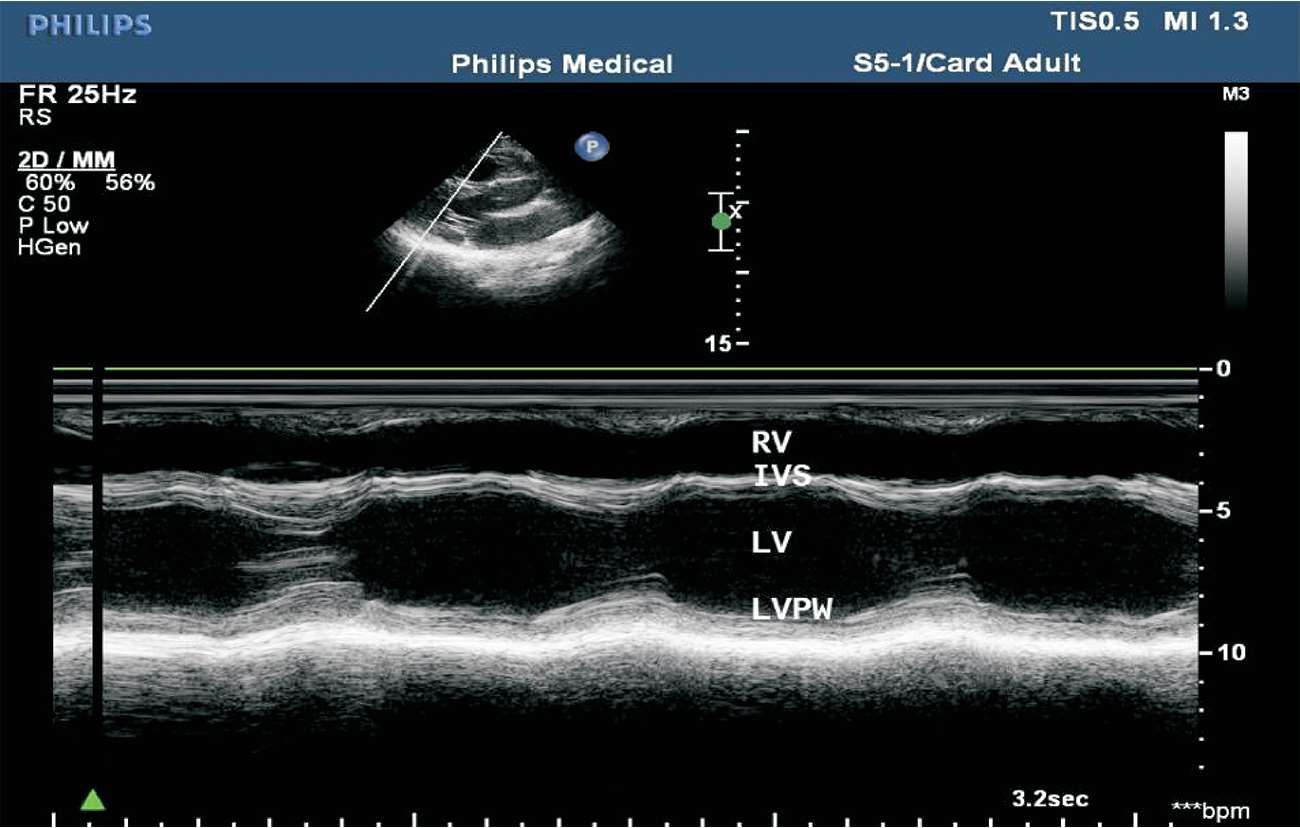

(1)胸骨旁左室长轴切面M型取样线置于二尖瓣腱索水平。

(2)结构从前到后依次为右室前壁、右心室、室间隔、左心室、左室后壁等。其中右心室大小及室间隔厚度应于舒张末期测量。可分别测量舒张末内径和收缩末内径以衡量左心室大小(见图1-24)。

图1-24 心室波群(RV:右心室;IVS:室间隔;LV:左心室;LVPW:左室后壁)

(1)M型超声心动图,适用于左心室无节段性运动异常者。取标准胸骨旁左心室长轴切面,取样线置于二尖瓣腱索水平,测量左心室舒张末期内径(LVD)与收缩末期内径(LVS),根据测量内径推算左心室舒张末期及收缩末期的容量,再根据左心室舒张末期容量及收缩末期容量的变化求出心输出量(见图1-36)。